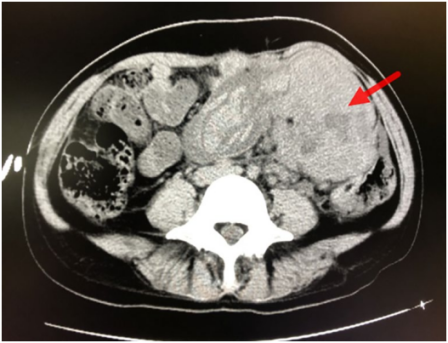

遂进行补液和抗休克治疗。胸部CT显示双肺结节影,提示可能有转移。腹部盆腔增强CT显示乙状结肠恶性肿瘤(结肠癌?),经三维重建病变后肠系膜上动脉供血,乙状结肠和直肠下部病变显示大量凝块。其次,在肠系膜下动脉根部、腹膜后间隙和门腔静脉间隙周围可见多个肿大淋巴结,并伴有坏死,提示可能有转移。此外,肝脏有多个转移瘤,大网膜种植性转移。

在介入室进行肠系膜上、下动脉的急诊动脉造影,并通过持续向肠系膜下动脉泵入垂体后叶素进行止血治疗(图2)。12小时后,患者病情稳定,转入外科病房。

图2